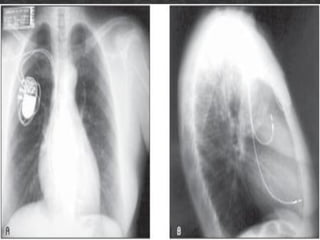

Marca-passo câmara única – o eletrodo é colocado no

ventrículo direito (parte inferior do coração).

Marca-passo câmara dupla – são colocados dois

eletrodos, um no átrio e outro no ventrículo direitos.

• O marca-passo é uma pequena caixa metálica que contém

circuitos eletrônicos e uma bateria. O marca-passo monitora

o coração continuamente, e envia um pulso elétrico para

compassar o coração quando seu próprio ritmo é

interrompido, está irregular ou muito lento.

• O cabo-eletrodo é um fio isolado que transporta o minúsculo

pulso elétrico do marca-passo ao coração para regular o

ritmo cardíaco.